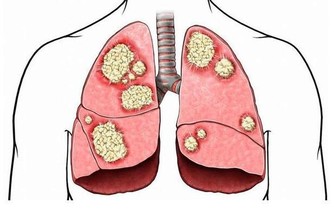

因為蝦體內多有肺吸蟲的囊蚴和副溶血性弧菌等,

如未煮熟,攝入就容易感染寄生蟲病和導致胃腸道中毒。